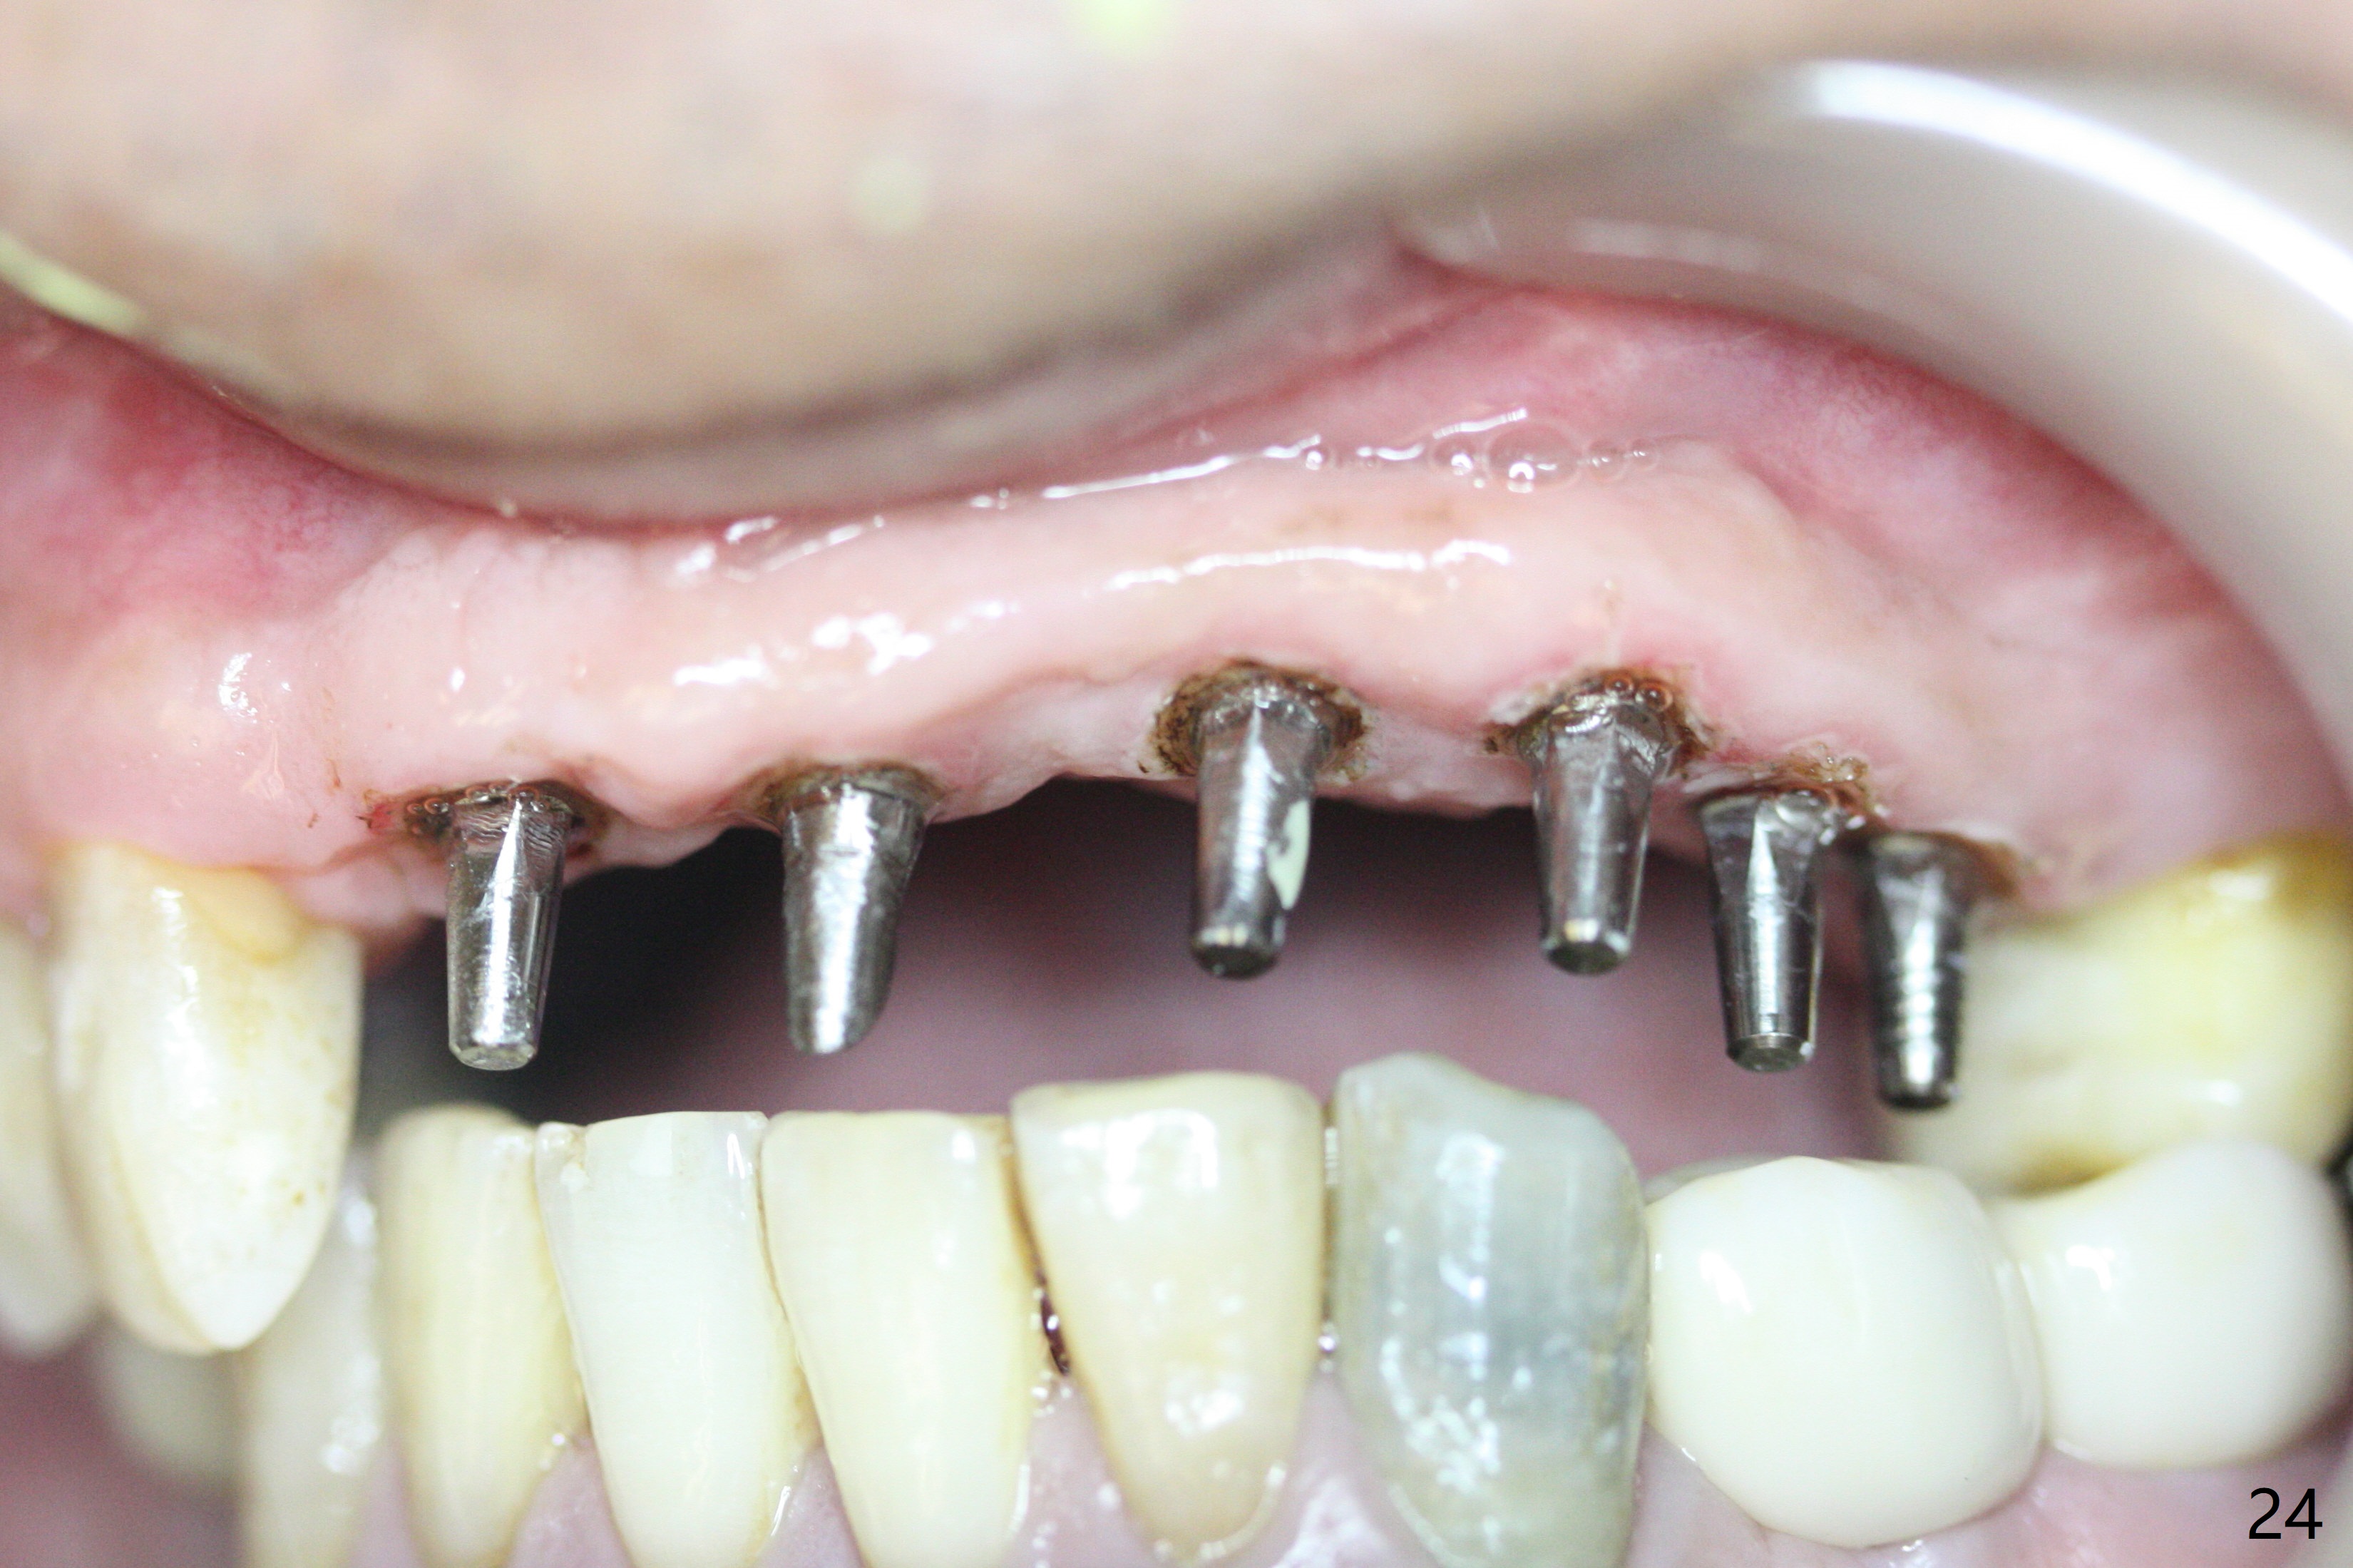

Impression is taken after laser gingivectomy 7.5 months postop (Fig.24).